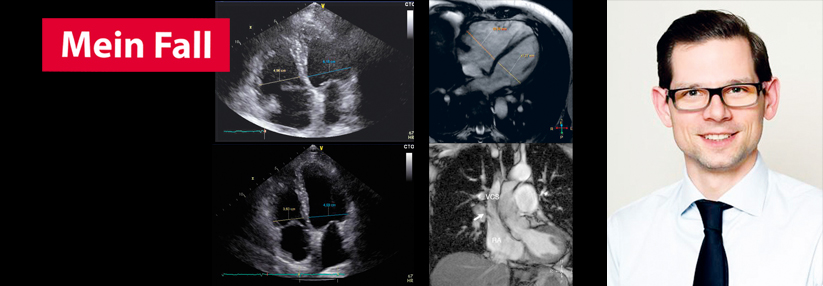

Der nachfolgende Fall einer 65 jährigen Patientin von Dr. Christopher Schneeweis zeigt, dass eine unklare Rechtsherzvergrößerung einer Abklärung…

mehr